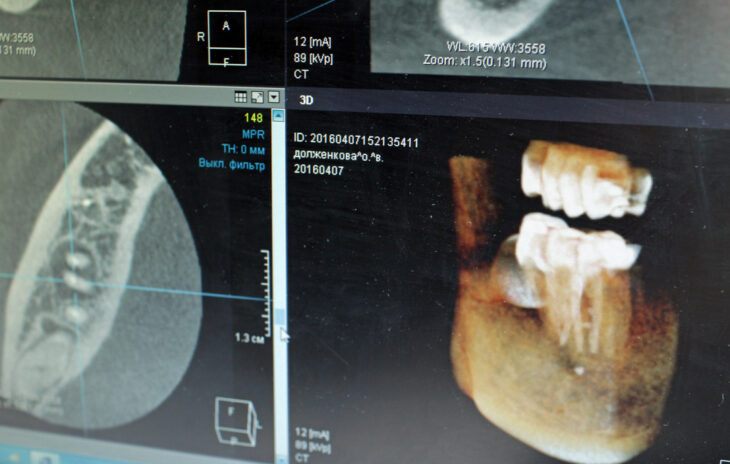

В телеэфире федерального канала показали историю пациента московской стоматологической клиники. Согласно сообщению, врачи сделали мужчине ряд дорогостоящих операций, без которых можно было обойтись. Эти медицинские манипуляции привели к ухудшению состояния его здоровья.

Авторы сюжета также заявили, что персонал клиники не выдает пациенту его медицинскую карту. Этот документ необходим для анализа правомерности и грамотности проведенного лечения. Ситуация получила серьезный отклик.